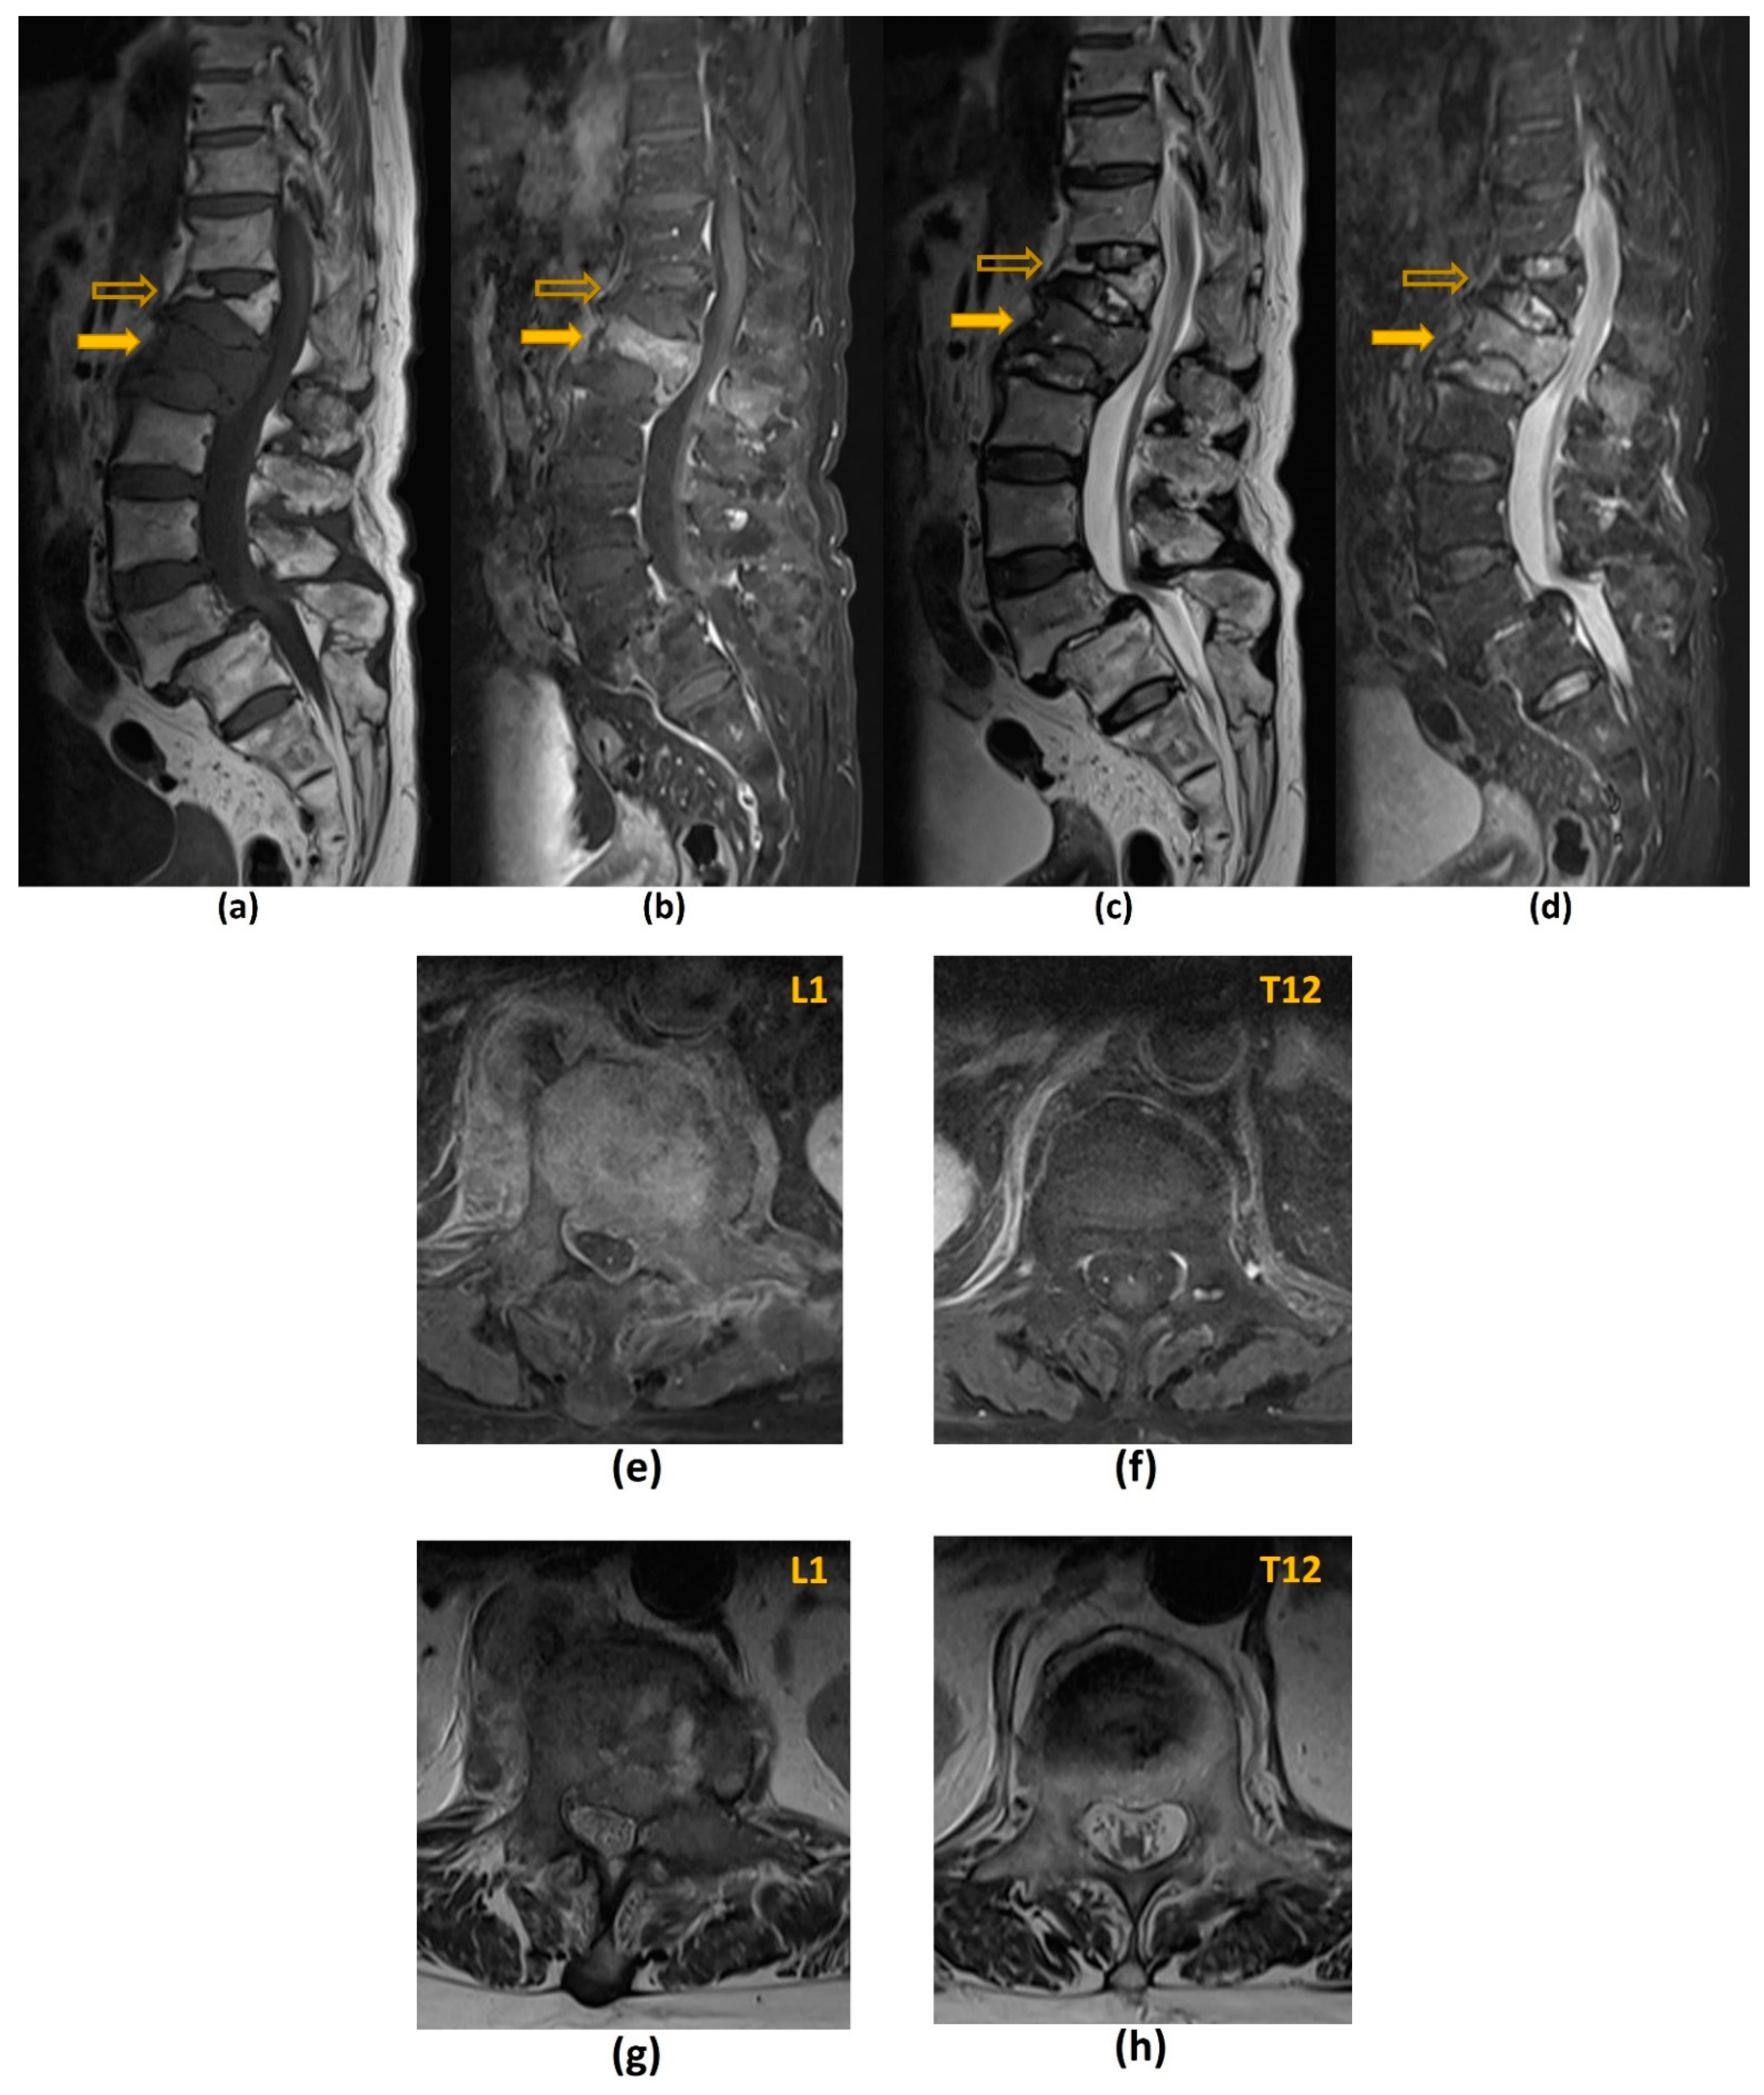

- Jung, H.S.; Jee, W.H.; McCauley, T.R.; Ha, K.Y.; Choi, K.H. Discrimination of metastatic from acute osteoporotic compression spinal fractures with MR imaging. Radiographics 2003, 23, 179–187. [Google Scholar] [CrossRef]

- Mauch, J.T.; Carr, C.M.; Cloft, H.; Diehn, F.E. Review of the Imaging Features of Benign Osteoporotic and Malignant Vertebral Compression Fractures. AJNR Am. J. Neuroradiol. 2018, 39, 1584–1592. [Google Scholar] [CrossRef]

| Benign Osteoporotic Compression Fracture | Malignant Vertebral Compression Fracture |

|---|---|

| Posterior retropulsion of bony fragments or a concave posterior border of the vertebral body | Expansile convex posterior cortex |

| Normal marrow signal intensity (or a well-demarcated regular margin separating the spared marrow and abnormal marrow within the fractured vertebra) | Reduced signal intensity on T1-weighted imaging reflecting an underlying marrow replacing process, particularly if the posterior elements are involved |

| Remains isointense post-contrast imaging | Heterogeneously increased enhancement of the vertebral body |

| Usually without involvement of the posterior vertebral elements | Involvement of the posterior elements |

| Presence of multiple compression fractures (with the notable exception of multiple myeloma) | Presence of other spinal metastasis |

| Presence of a T1-weighted and T2-weighted hypointense band (thought to represent cancellous bone compaction, fluid or gas-filled clefts) | Abnormal epidural or paraspinal soft tissue or enhancement |